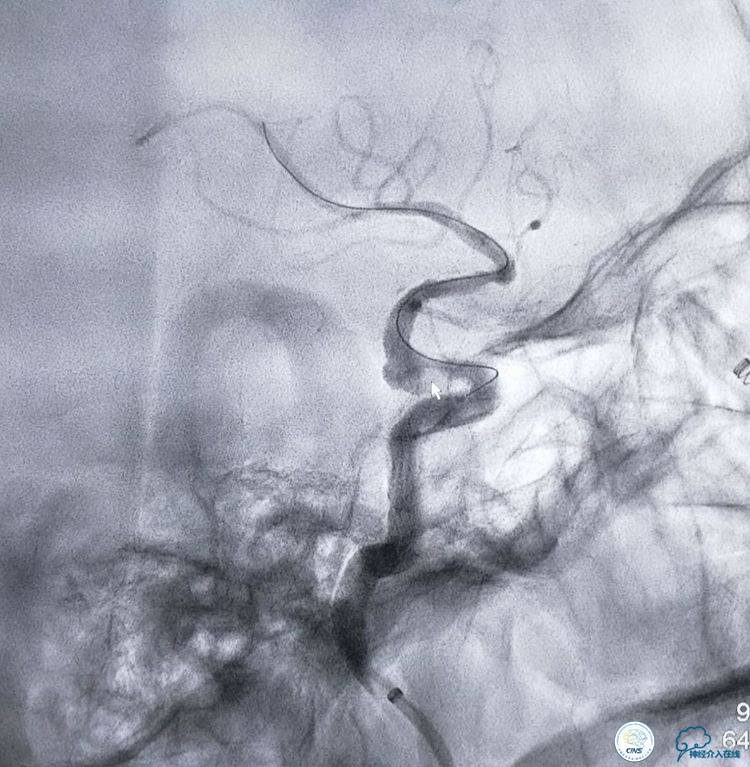

▼全麻后,导引导管到位以后,选择合适的工作角度。

▼将3米的微导丝超选择到大脑中动脉M2以远。

▼选择3×9mm Getway球囊进行扩张。

▼扩张后狭窄明显改善。